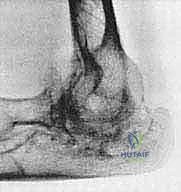

1. التخطيط الجراحي المسبق (Pre-operative Planning)

يتم إجراء صور أشعة سينية دقيقة (X-rays) وأحياناً تصوير مقطعي (CT Scan) لتقييم حجم العظام المتبقية وجودتها. في مرضى الروماتويد، يكون العظم غالباً هشاً (Osteoporotic)، مما يتطلب تخطيطاً دقيقاً لاختيار حجم ونوع المفصل الصناعي المناسب (مفصل متصل Linked أو غير متصل Unlinked).